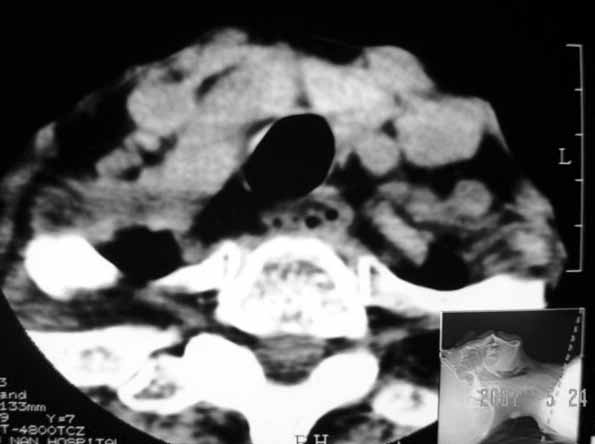

以下是引用jw-830在2007-5-24 15:33:00的发言:[br]右侧甲状腺增大,内可见低密度,病灶与周围软组织界线欠清晰,建议增强扫描除外甲状腺癌

以下是引用adams在2007-5-24 17:15:00的发言:[br]支持“ 右侧甲状腺增大,内可见低密度,病灶与周围软组织界线欠清晰,建议增强扫描除外甲状腺癌”。 [br] [br] [br][br] [br] [br]

以下是引用苯小孩在2007-5-24 15:26:00的发言:[br]左侧甲状腺腺癌或瘤,建议穿刺或核素进一步检查.